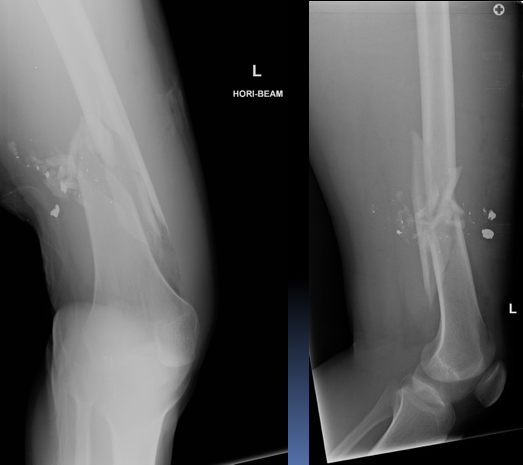

A 30 year old man presented to the ED with left knee pain after a cycling accident.

On examination there was no deformity, but it was painful for him to weight-bear. Movements of his knee were painful, and this limited his movements.

What is a lipohemarthrosis?

Results from an intra-articular fracture with escape of fat and blood from the bone marrow into the joint, and is most frequently seen in the knee.